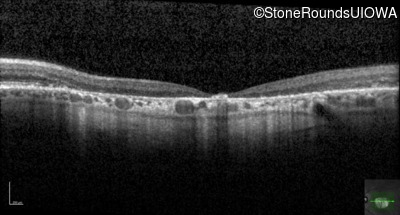

Age at visit: 52 years

This 52 year old man first noticed reduced visual acuity at age 21.

Age at visit: 54 years

Age at visit: 59 years